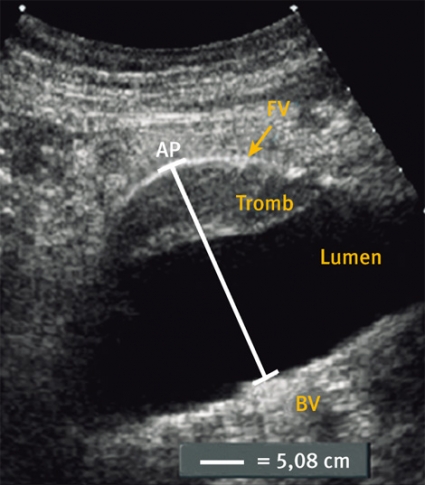

Ultraljudsundersökningen vid screening (Figur 2) skiljer sig från en fullvärdig aortaundersökning såtillvida att dess primära syfte är att med hög säkerhet utesluta sjukdom. Vid screening läggs transduktorn i kärlets längsriktning (Figur 2 a) och maximal infrarenal anteroposterior diameter mäts enligt principen »leading edge to leading edge« (Figur 3). Måttet anges på ett protokoll, som också innehåller uppgifter om eventuella visibilitetsproblem samt undersökarens initialer. Vid diameter ≥25 mm anges också diametern med transduktorn vinkelrätt mot kärlet (Figur 2 b).

I samma seans görs då också en utvidgad undersökning omfattande diametern av »aortahalsen« (segmentet nedanför njurartärernas avgång) och den suprarenala aortadiametern, för att få en uppfattning om den relativa diametern, samt av iliaca-kärlen. Samtliga mätningar (såväl positiva som negativa) dokumenteras genom en pappersutskrift.